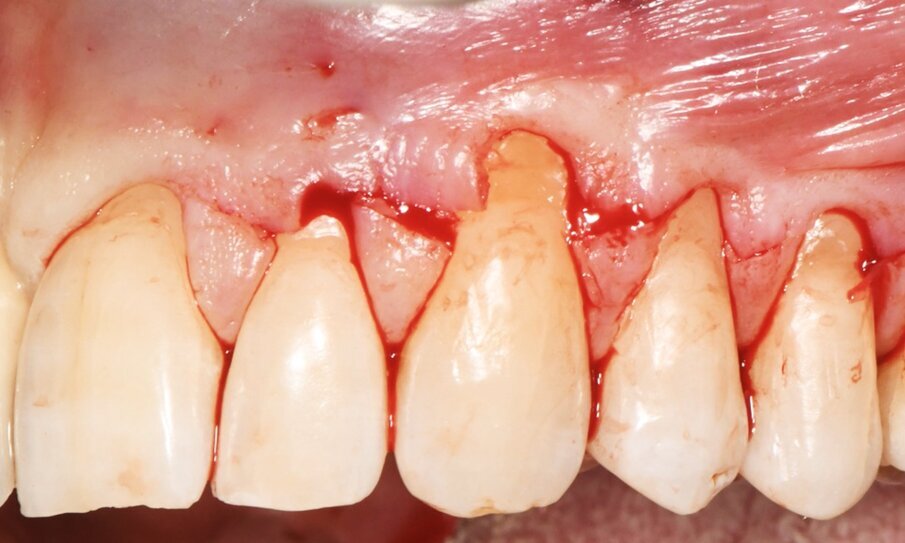

Dopo avere eseguito le incisioni primarie si provvedeva a elevare e mobilitare il lembo con tecnica mista: a spessore parziale in corrispondenza delle papille fino all’altezza del margine apicale delle recessioni, a spessore totale fino al raggiungimento della linea muco-gengivale e infine a spessore parziale apicalmente alla linea muco gengivale per la mobilizzazione in direzione apicale del lembo (Fig. 4). Il sito ricevente è stato trattato mediante levigatura radicolare meccanica della quota di radice esposta in cavo orale dalla recessione e disepitelizzazione delle papille anatomiche. Successivamente la matrice tridimensionale collagenica veniva sagomata in modo da coprire le radici esposte dal 23 al 25 e stabilizzata in sede con suture alla base delle papille anatomiche (Fig. 5). La matrice collagenica, una volta posizionata asciutta nel sito ricevente in modo da facilitarne la sutura, aderiva naturalmente ai tessuti. La matrice veniva suturata senza tensione con punti staccati, alla base delle papille anatomiche, con un filo Polyglactine 6-0 ago 3/8 Reverse - cut Surgicryl (SMI AG Steinberg 8 - 4780 ST.VITH) (Fig. 6).

Fig. 5 - Apposizione della matrice collagenica tridimensionale di origine equina, fissata con punti staccati alla base delle papille anatomiche, imbibita di sangue per ottenere la copertura radicolare degli elementi 23-25.

Fig. 6 - Il lembo a busta è posizionato coronalmente e fissato in sede con punti sospesi.